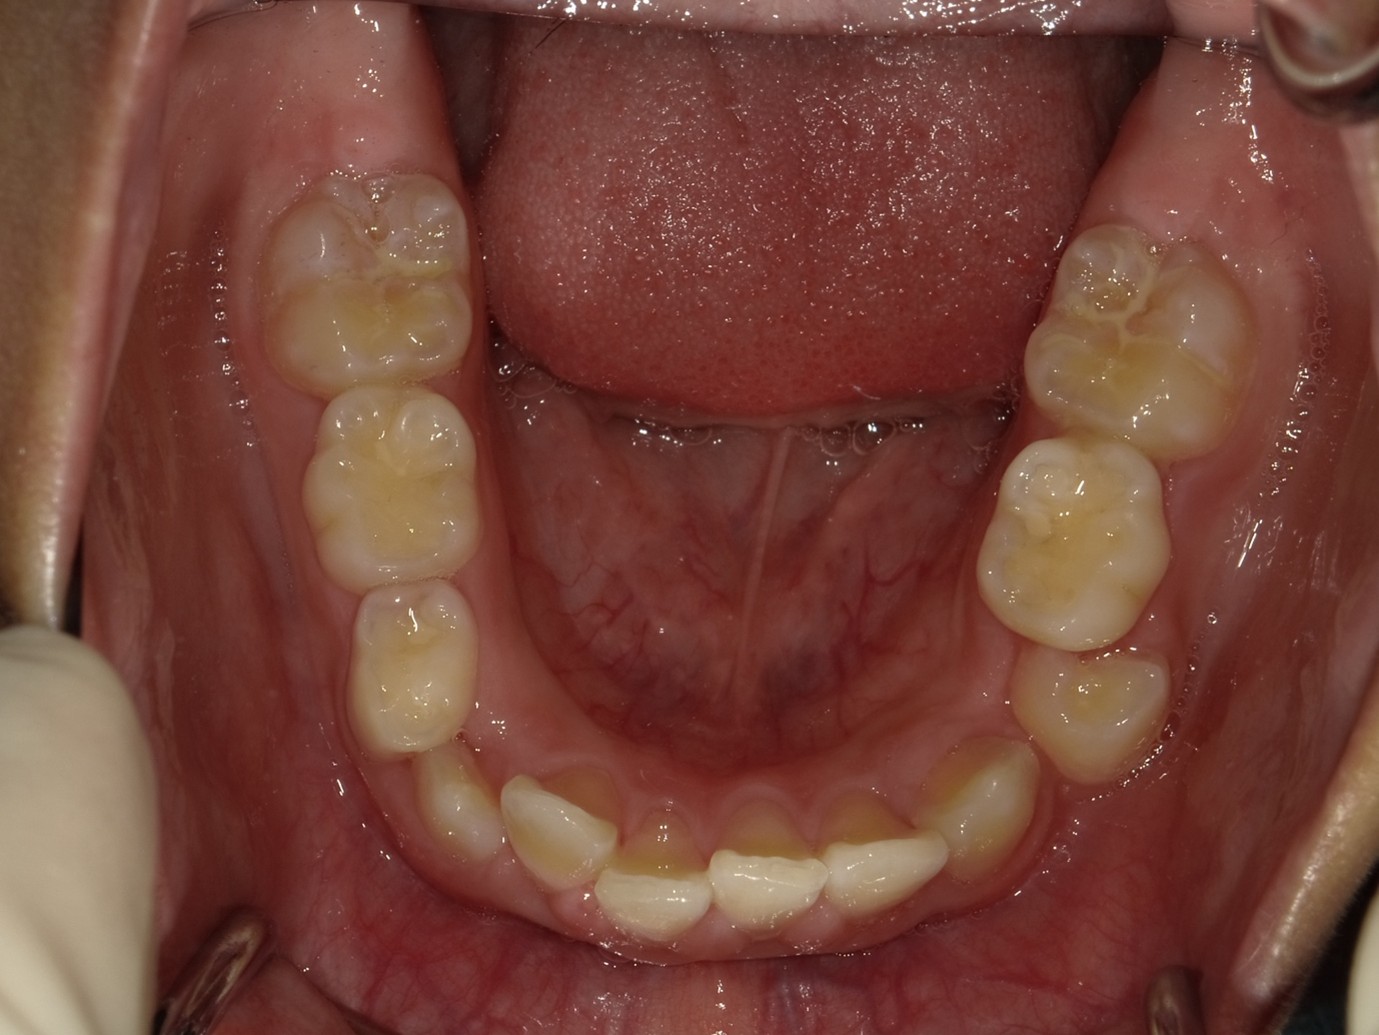

| 症例分類 | 過蓋咬合 |

|---|---|

| 主訴 | 他の歯科医院で咬み合わせを指摘された |

| 年齢 | 10歳10ヶ月 |

| 性別 | 男性 |

| 抜歯部位 | なし |

| 使用装置 | 拡大装置、咬合斜面板(取り外し式の矯正装置) |

| 治療期間 | 3年4ヶ月 |

| 保定装置 | 咬合斜面板 |

| 費用 | 相談料0円、検査料55,000円 動的矯正治療費330,000円 調整料6,600円×30回分 保定装置料0円 |

| リスク・注意点 | 上の顎の大きさに対して下の顎が小さく、過蓋咬合が生じています。これらを改善するために、幅の狭搾している歯列を側方に拡大したのち、下顎の成長を促進しました。

歯の動き方には個人差があり、予想された治療期間が延長する可能性があります。 治療中は矯正歯科装置が歯の表面に付いており、歯が磨きにくくなるため、むし歯や歯周病が生じるリスクが高まります。ハミガキを適切に行ってお口の中を常に清潔に保ち、さらに、かかりつけ歯科医に定期的に受診することが大切です。 矯正歯科装置の使用状況、定期的な通院など、矯正歯科治療には患者さんの協力が必要であり、それらが治療結果や治療期間に影響します。 治療の経過によっては当初予定していた治療計画を変更する可能性があります。保定装置の装着時間が十分確保できない場合、歯並びや、咬み合せの「後戻り」が生じる可能性があります。 上下両側第二大臼歯の萌出を観察する必要があります。(治療後の写真は成人矯正開始直前の資料です。) |